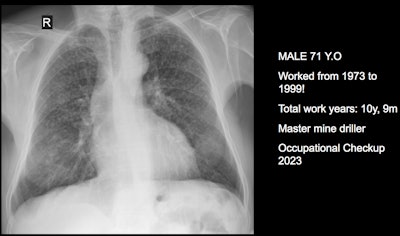

Three clinical cases courtesy of Dr. Luis Antonio Campos Calderon.

The International Labor Organization (ILO) International Classification of Radiographs of Pneumoconioses is used for epidemiological studies, screening, and surveillance of workers exposed to dust in the workplace, and clinical purposes, and the National Institute for Occupational Safety and Health (NIOSH) B Reader Program certifies physicians in the ILO classification system. Each case should discuss its ILO classification and brief comments about the workflow, he noted.

"Pneumoconiosis often develops slowly, and symptoms may not appear until significant damage has occurred. Early detection is crucial but can be difficult due to limited resources and awareness," Campos explained. "This diagnosis can be fraught because in Peru workers diagnosed with pneumoconiosis have rights to compensation and healthcare under current labor laws and social security systems. However, navigating the legal and bureaucratic processes to claim these benefits can be complex and challenging."

The main diagnostic criteria are: Work history (minimum 10 years exposure to silica dust or other particles); chest x-ray (micronodular pulmonary fibrosis, coded according to ILO classification); progression (image profusion increases over time, even after exposure cessation; irreversibility (disease is progressive and irreversible, no stable pneumoconiosis over time).